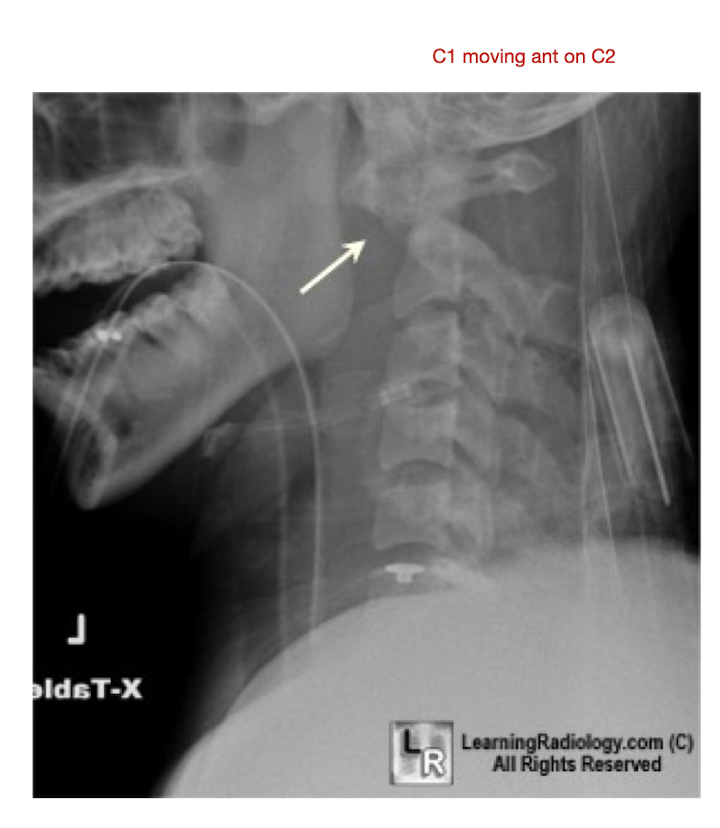

C/S: RA

What is it?

What does RA cause?

What 3 structures does it affect?

What is it?

Erosion and narrowing of the facet jts

Cause:

Increased Lig Laxity

Atlantoaxial Jt

Laxity of the Transverse Lig

Anterior Subluxation of C1 on C2